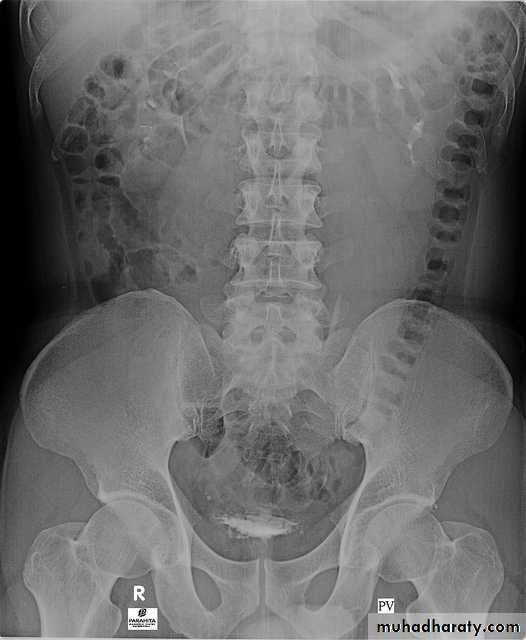

5. A full bladder film (with the urinary bladder fully distended with contrast)

4. Bladder

The bladder is a centrally located structure.Smooth in outline.

Smooth indentation from above by uterus on the right or sigmoid colon on the left and from below by muscles of the pelvic floor is normal.